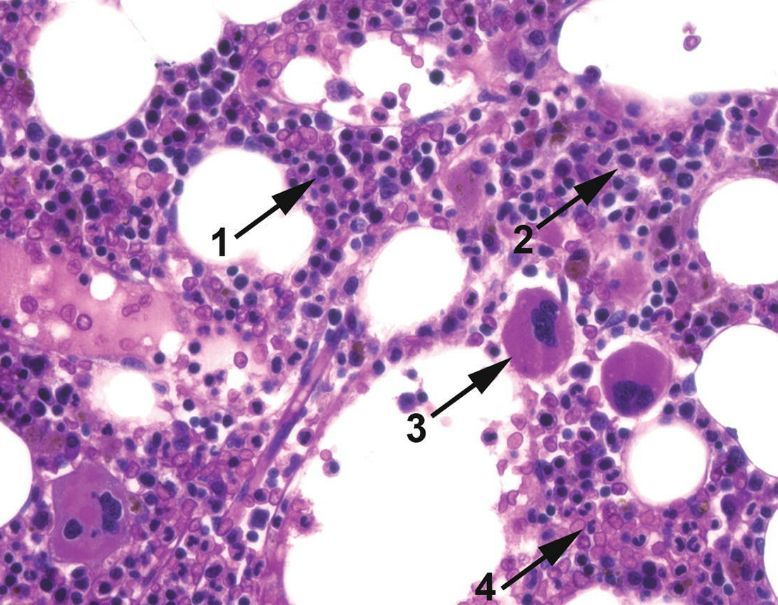

Erythroblasts

Often described as having “royal blue” cytoplasm and very round nuclei.